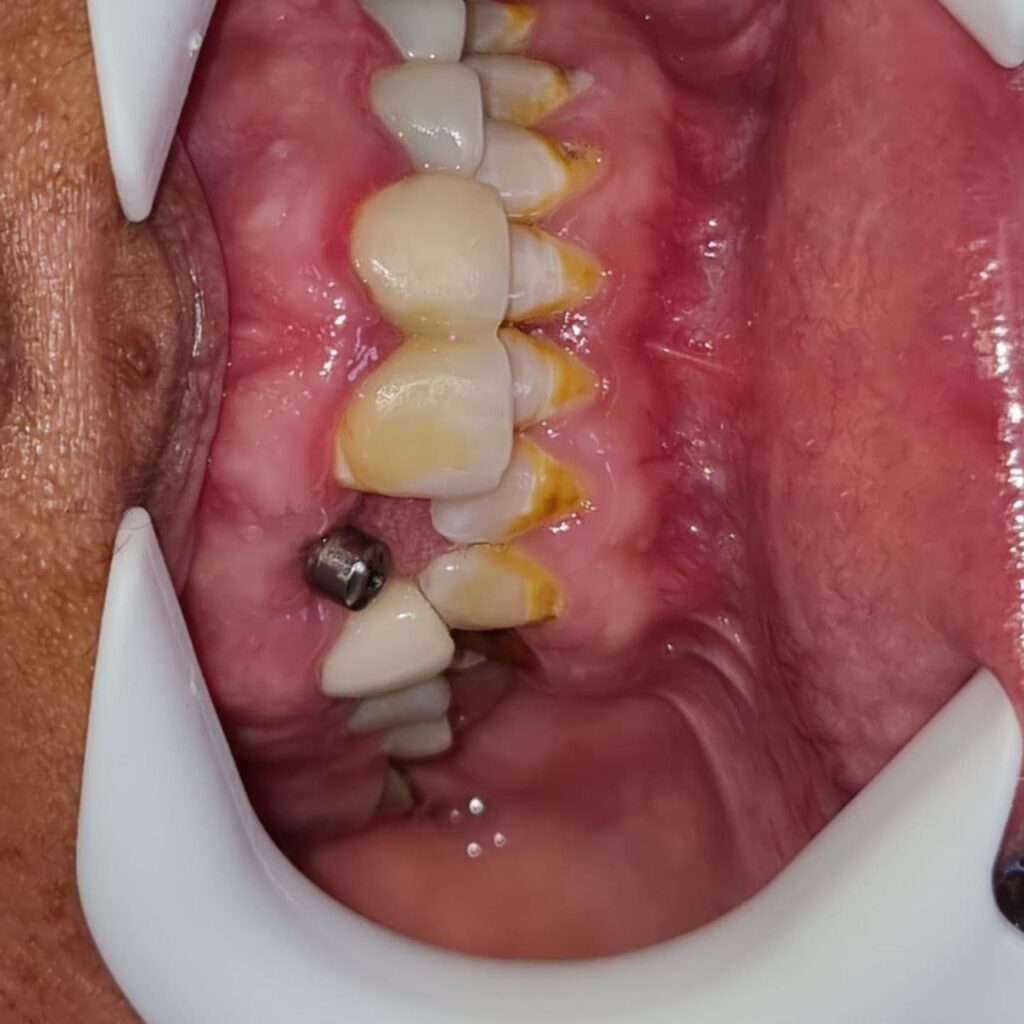

کاشت ایمپلنت دندان

اطمینان حاصل کردن از اینکه دندانهایتان به نحوی زیبا و طبیعی جایگزین شدهاند، از اهمیت بسیاری برخوردار است. ایمپلنت دندان به عنوان یک روش درمانی دائمی در دندانپزشکی شناخته میشود که حاصل آن، یک دندان زیبا و طبیعی در دهان شما خواهد بود.

هرچند که این روش درمانی هزینهی بیشتری نسبت به روشهای دیگر دارد، اما ارزش زیبایی که ایجاد میکند، قابل انکار نیست. ایمپلنتها به قدری شبیه به دندانهای طبیعی هستند که به سختی میتوان آنها را از دیگر دندانها تشخیص داد.